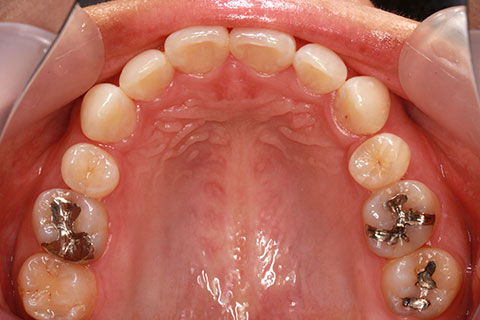

ハーフリンガル矯正2:上の歯のみ舌側矯正で治療(矯正期間18ヶ月)

- 年齢・性別

- 23歳女性

- 治療期間

- 1年6ヶ月

- 抜歯

- 上顎4番

- 治療費

- 110万円(税込み)

- 備考

- ハーフリンガル矯正

- 治療内容

- 上下前歯部凸凹の改善

- 施術の副作用(リスク)

- 裏側矯正の特性上、表側矯正と比較すると治療期間が長くかかる場合が多い。